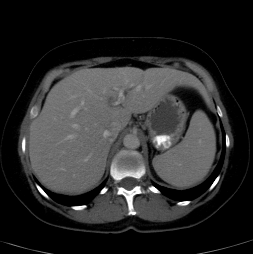

In clinical routine, manual or semi-manual segmentation techniques are applied to interprete CT and MRI images that have been acquired in the diagnosis of the liver. These techniques, however, are subjective, operator-dependent and very time-consuming. In order to improve the productivity of radiologists, computer-aided methods have been developed in the past. However, an automated robust segmentation of combined liver and lesion remains still an open problem because of challenges as a low-contrast between liver and lesion, different types of contrast levels (hyper-/hypo-intense tumors), abnormalities in tissues (such as after surgical resection of metastasis), size and varying number of lesions. As shown in figure 1 the heterogeneity in liver and lesion contrast is very large among subjects. Different acquisition protocols, differing contrast-agents, varying levels of contrast enhancements and dissimilar scanner resolutions lead to unpredictable intensity differences between liver and lesion tissue. This complexity of contrast differences make it difficult for intensity-based methods to generalize to unseen test cases from different clinical sites. In addition, the varying shape of lesions due to irregular tumor growth and response to treatment (i.e surgical resection) reduce efficiency of computational methods that make use of prior knowledge on lesion shape.

Figure 1: Liver and liver lesions slices in CT and diffusion weighted DW-MRI as well as the corresponding histogram for liver and lesions pixels in the respective modality. The shape, size and level of contrast vary for different lesions. As the histograms indicate, there is a significant overlap between liver and lesion intensities, leading to a low overall contrast.